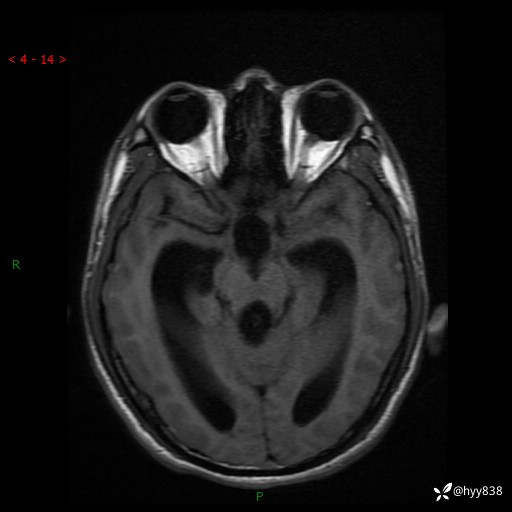

病例花季少年,头痛伴间断性呕吐1月余。四脑室占位,容易诊断错---结果公布~

性别:男

年龄:17岁

简要病史:头痛伴间断性呕吐1月余,外院CT提示颅脑占位

颅脑MRI平扫+增强